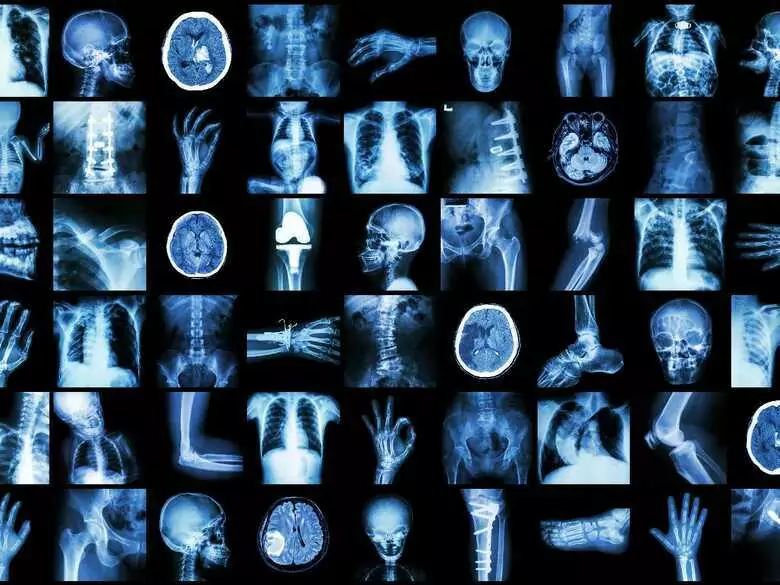

X-ray images